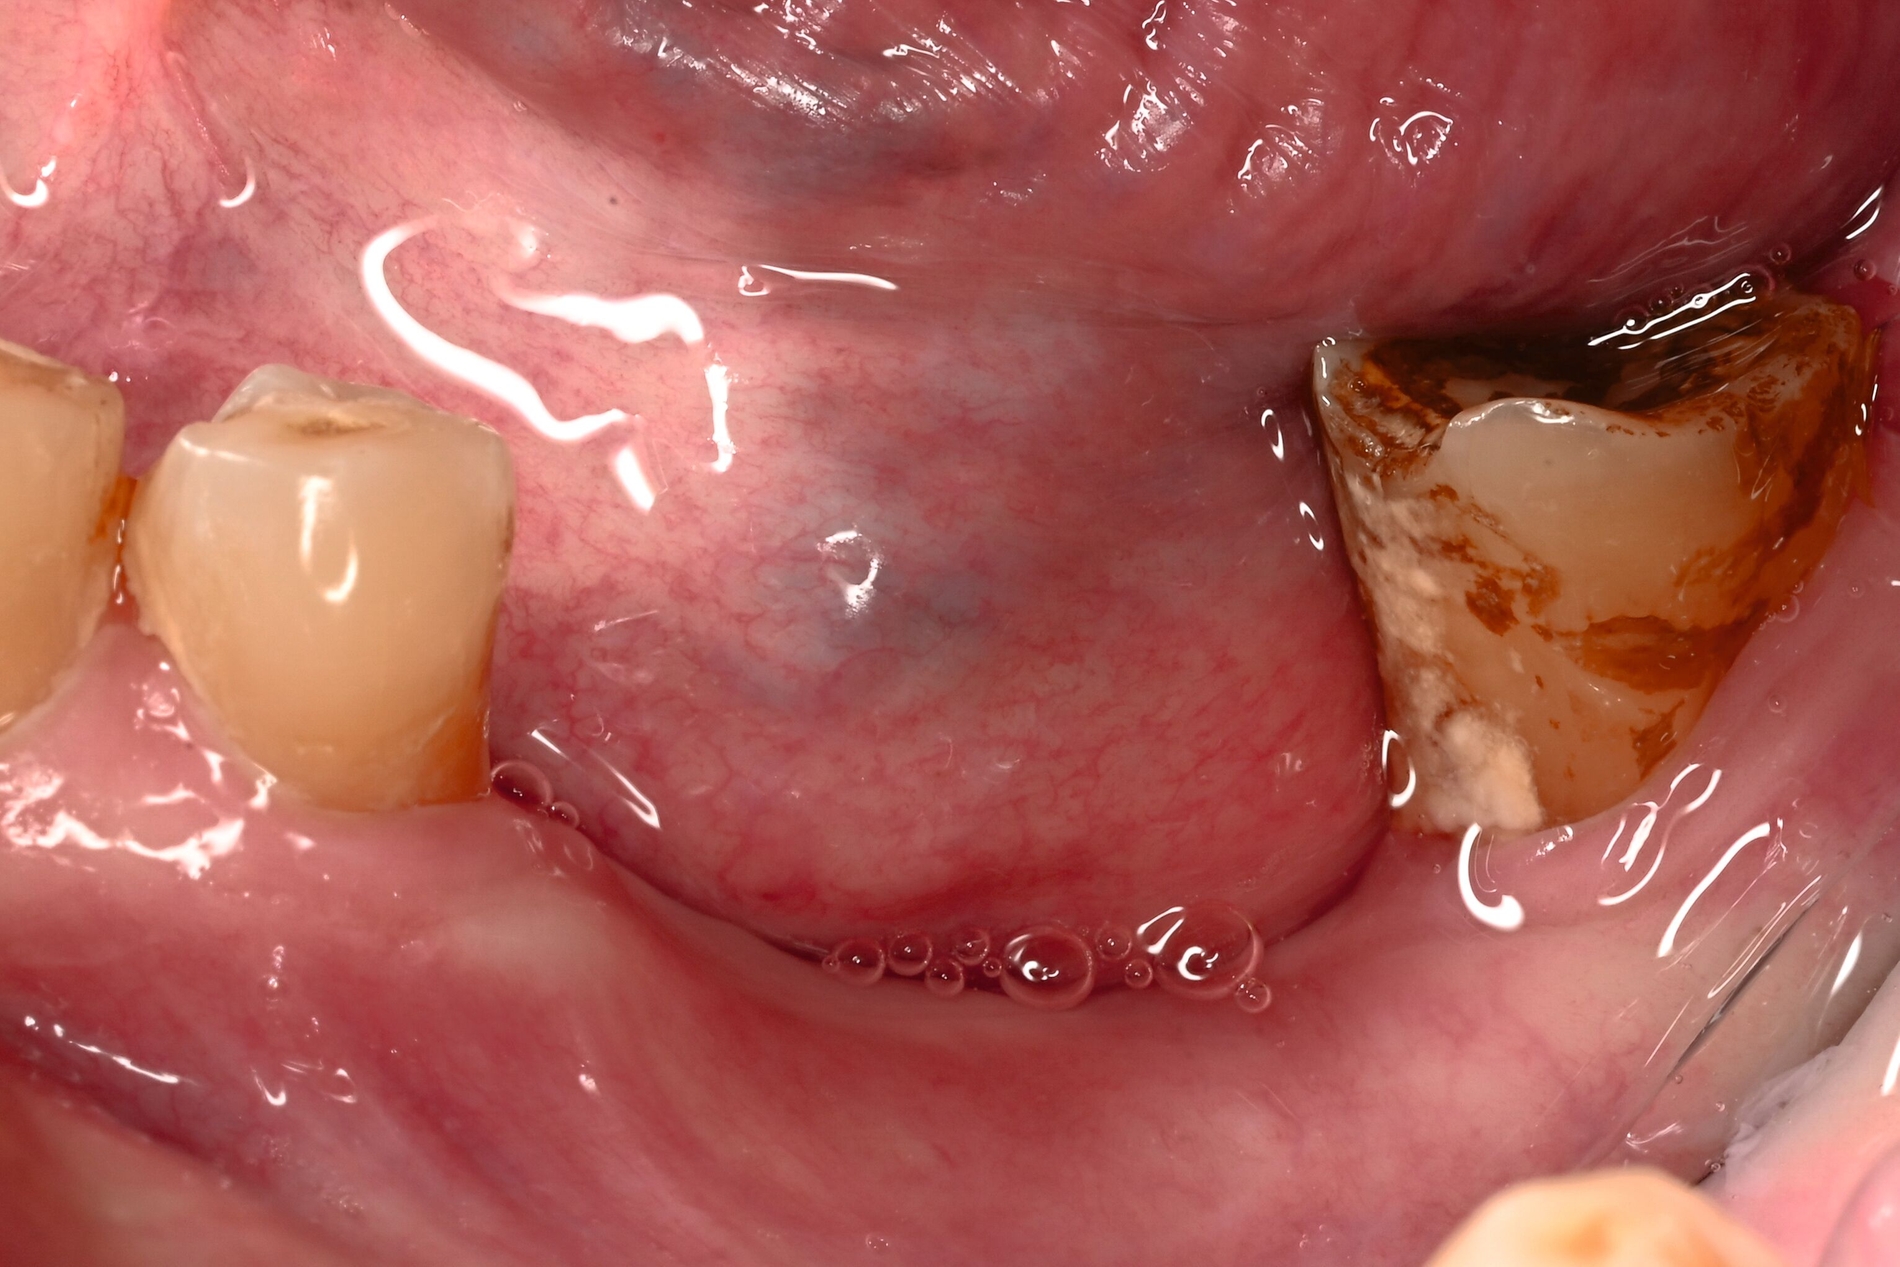

Der Patient stellte sich mit freiliegendem Knochen in Regio 43 bis 47 und mehreren gelockerten Zähnen vor. 45 und 46 waren devital. Als klinische Besonderheit fiel auf, dass sich innerhalb der Nekrosezone kleinflächige Weichgewebsareale darstellten, die in dieser Form bei klassischen Osteonekrosen üblicherweise nicht beobachtet werden. Eine klassische Vincent-Symptomatik bestand nicht. Drei Wochen zuvor war eine Herpes-Zoster-Infektion dermatologisch diagnostiziert und zunächst stationär behandelt worden. Der Patient erhielt eine intravenöse, antivirale Therapie, die bei Entlassung oralisiert wurde.

Zum Zeitpunkt der Erstvorstellung in der kieferchirurgischen Ambulanz zeigten sich keine klassischen Herpes-Zoster-Effloreszenzen im Gesicht. Eine antiresorptive Therapie oder Bestrahlung lag nicht vor, sodass eine Herpes-Zoster-assoziierte Osteonekrose im Sinne einer Ausschlussdiagnose festgestellt wurde. Anamnestisch bestand ein gut eingestellter Diabetes mellitus Typ 2 als potenziell immunkompromittierende Grunderkrankung. Die Knochenszintigrafie zeigte eine deutliche Stoffwechselsteigerung im betroffenen Bereich, vereinbar mit einer infizierten Osteonekrose.